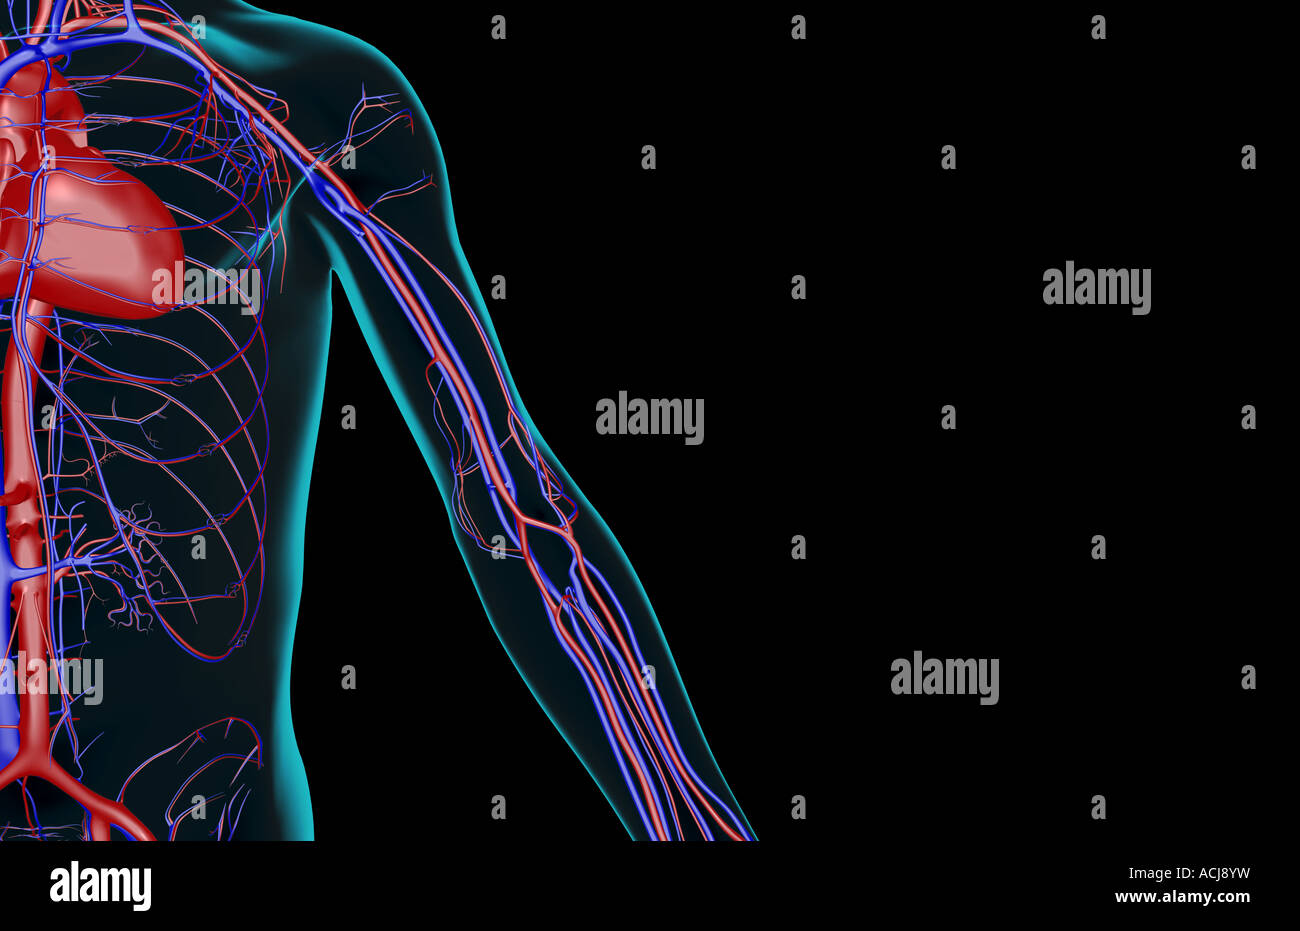

RMJE7CWP–Der Plexus brachialis ist ein Nervennetz im Nacken- und Schulterbereich, das für die motorischen und sensorischen Funktionen der oberen Extremität von wesentlicher Bedeutung ist. Das Bild zeigt den Plexus brachialis an seiner anatomischen Position.